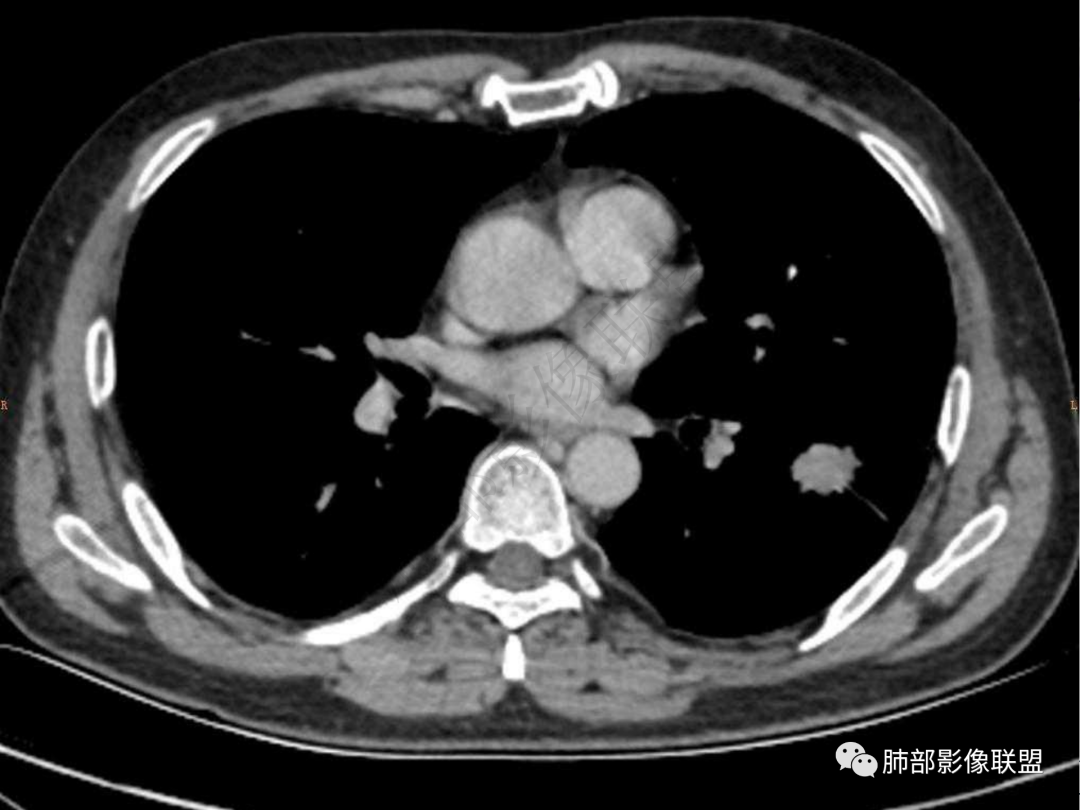

4.实性部分不均匀环形强化并显示一小范围低密度坏死区或空洞。较之肺窗,整体纵隔窗范围较小,提示病灶并不十分密实。抑或为不同时段图像。

六:增强扫描:

肺脓肿:环形强化,强化较显著。如出现明显囊壁样强化甚至边缘“憩室”样突出,高度支持肺脓肿。